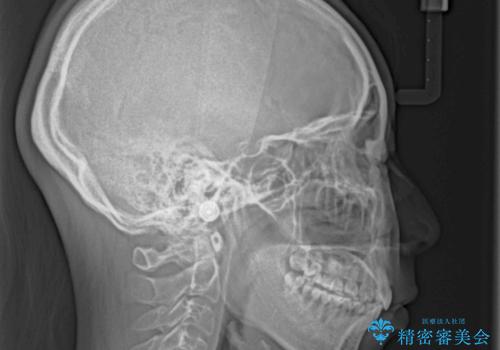

非常に大きな虫歯のあった下顎大臼歯は、根管治療を行い、矯正治療後にオールセラミッククラウンにて補綴治療を行いました。

当初予定では3年以上かかるとお伝えしておりましたが、スムーズに歯列が整い、2年強で終了することができました。